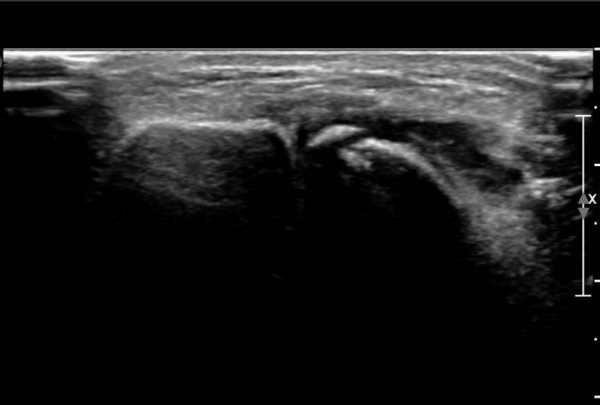

¾Õ°æ°ñºñ°ñÀδë Á¾´Ü¸é°Ë»ç¿¡¼­ °æ°ñºñ°ñÀδëÀÇ  Àú¿¡ÄÚ  ºÎÁ¾ ¹× ÀδëºÎÂøºÎ °æ°ñÀÇ

°ß¿­°ñÀýÀÌ  °üÂûµÊ(»çÁø 2, 3, 4)